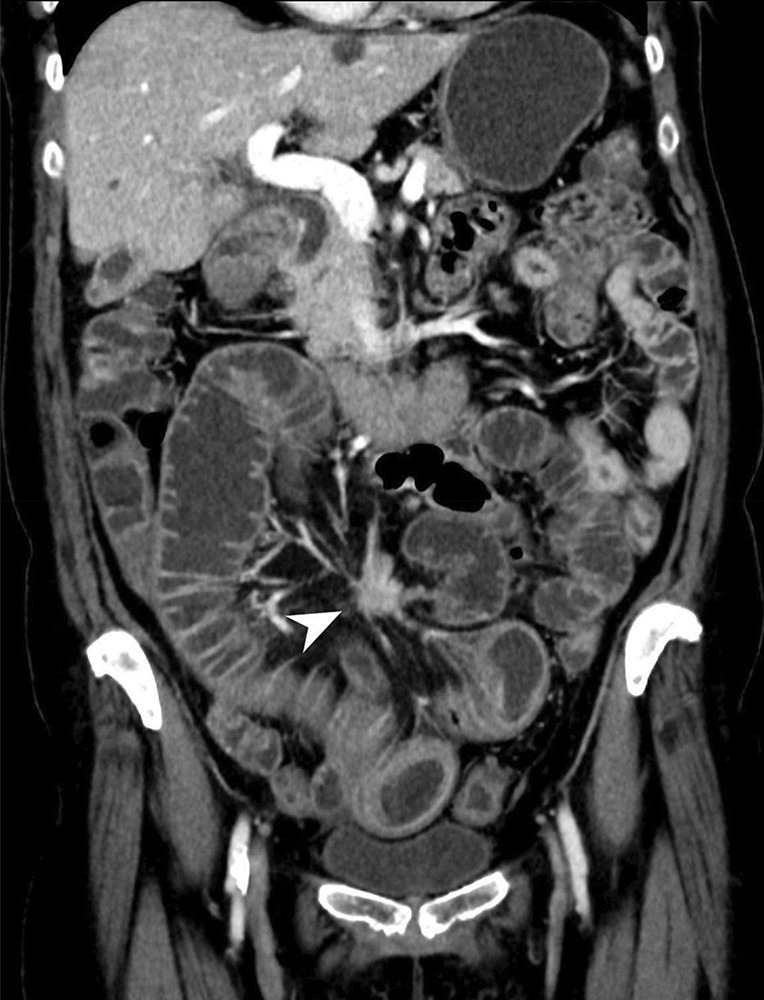

教学点:CT小肠造影/小肠灌肠术可充分评估小肠神经内分泌肿瘤及肠外异常。

Teaching point: CT enterography/enteroclysis allows adequate evaluation of neuroendocrine small bowel tumor and extra-enteric abnormalities.